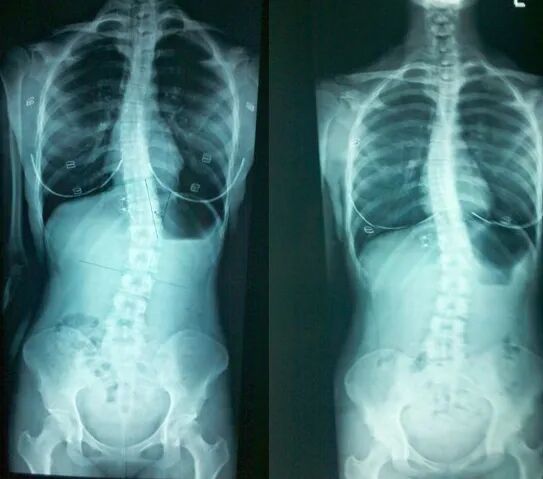

[] 脊椎側彎(scoliosis)是指人的有側向的彎曲 ,其形狀可能是S形或是C形。

突發性脊椎側彎 是指患者先天脊椎發育異常,但成因不明,可能與遺傳、發育期間骨骼 畸形等問題有關。

此類脊柱側彎原因不明,但相信與基因、家族史、骨膠原蛋白構造異常、肌肉柔韌度異常、內耳平衡異常等方面有關,故此Claudia 强調,每人接受介入性治療後的成效都可能有所不同,但仍可就著不同徵狀針對關節活動功能、肌肉協調、平衡力協調等作改善。

脊椎手術的目的並非要求呈一直線,而是要處於平衡的狀態,而融合手術是防止脊椎畸型更加嚴重。